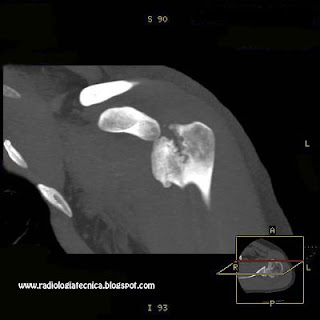

Fractura de Cabeza Humeral vista por TC

En esta ocasión nuestro colaborador Juan Verde, nos envia las siguientes imagenes de un TAC de hombro, en la que podemos apreciar una pequeña fractura con desplazamiento de la cabeza humeral.

En la reconstrucción volumetrica se observa claramente el detalle de la fractura.